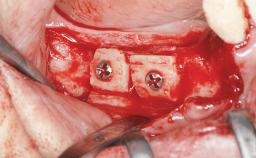

| Bone Augmentation | Horizontal|Staged|Vertical |

| Augmentation Materials | Autogenous chips|Autogenous block(s)|Xenogenous |